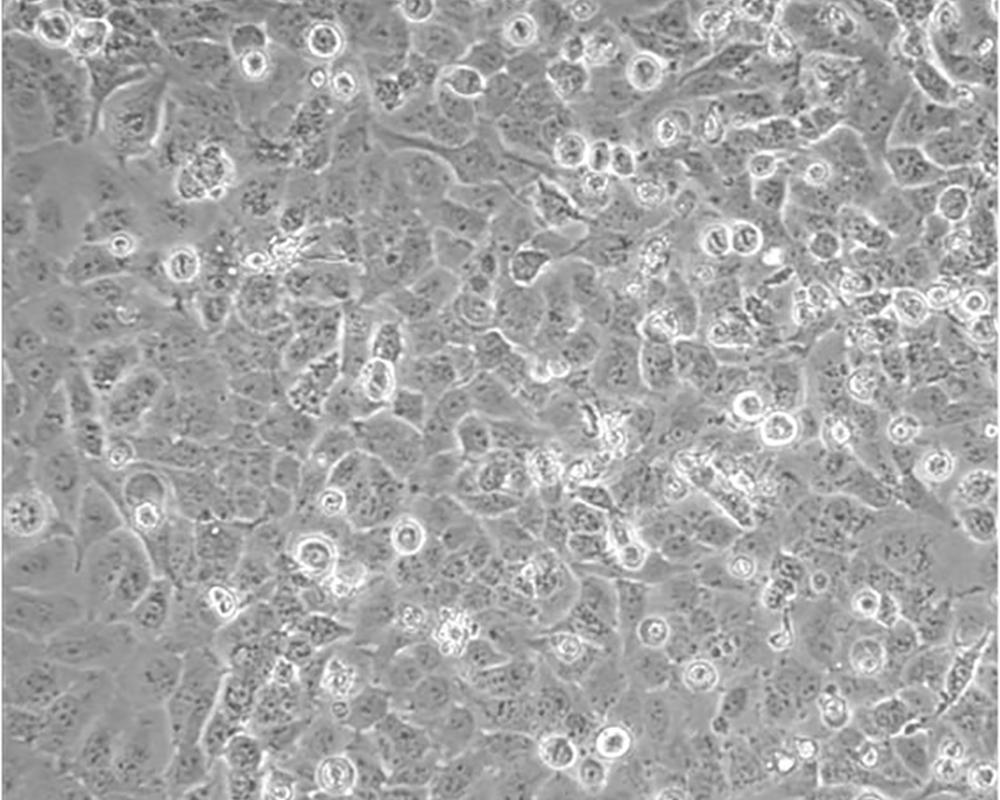

NCI-H23

形態(tài)特征 epithelial

細(xì)胞描述 該細(xì)胞源于一位51歲患有非小細(xì)胞肺癌黑人男性患者的治療前的腫瘤組織,表達(dá)C-myc、L-myc、v-src、v-abl、v-erb B、c-raf 1、Ha-ras、Ki-ras、N-ras RNAs;該細(xì)胞攜帶K-ras 12突變;p53基因246位密碼子突變ATC→ATG;表達(dá)PDGF A和B鏈的異源mRNA;表達(dá)TGFα、TGFβ和EGFR;角蛋白 5、8和18陽性,波形蛋白陽性,神經(jīng)絲蛋白陰性,左旋多巴脫氫酶陰性;據(jù)報(bào)道,在軟瓊脂中該細(xì)胞形成克隆的效率為9.7%。